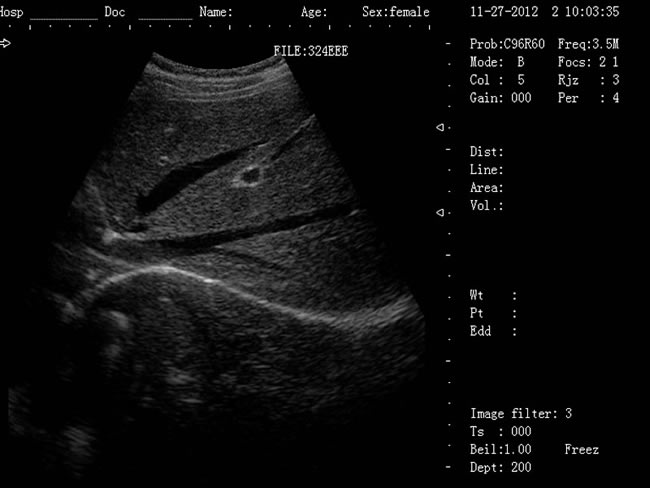

| 老式的b超機(jī)黑白要多少錢?已被新型B超機(jī)所取代! |

老式的b超機(jī)黑白要多少錢?老式的B超機(jī)是CRT顯示器,CRT顯示器學(xué)名為“陰極射線顯像管”,是一種使用陰極射線管的顯示器。現(xiàn)在科技進(jìn)步,已經(jīng)慢慢被新型顯示器所取代。老式的黑白b超機(jī)CRT顯示器主要有五部分組成:電子槍,偏轉(zhuǎn)線圈,蔭罩,高壓石墨電極和熒光粉涂層及玻璃外殼。感謝大家對(duì)我司CRT顯示器相關(guān)產(chǎn)品長(zhǎng)久以來(lái)的支持與厚愛,該系列機(jī)型因順應(yīng)市場(chǎng)的需求,已經(jīng)無(wú)法滿足客戶的生產(chǎn)需求。該系列機(jī)型正式停產(chǎn),后期不再供應(yīng)該型號(hào)的儀器。給廣大的新老客戶造成的不便敬請(qǐng)諒解。應(yīng)廣大用戶的需要,CRT相關(guān)產(chǎn)品的售后服務(wù)依然支持,同時(shí)保留儀器后期的維修部件。

徐州大為DW-500筆記本b超機(jī) 1、DW-500產(chǎn)品特點(diǎn): (1)DW-500是一款高陣元、高清晰度、多功能的筆記本式超聲診斷儀。 (2)它的小巧輕便,圖像清晰,操作方便、續(xù)航能力強(qiáng),在城市、鄉(xiāng)鎮(zhèn)、戶外等,各種環(huán)境下會(huì)診的超強(qiáng)優(yōu)越性。 (3)多種充電方式更保證了在不同環(huán)境下檢查會(huì)診。 2、DW-500新增3大看點(diǎn): (1)5-7小時(shí)超長(zhǎng)待機(jī)時(shí)間 (2)12.1英寸LED液晶顯示器 (3)全數(shù)字96陣元 3、一流的數(shù)字成像技術(shù),圖像更清晰 (1)DBF全數(shù)字波束形成 (2)DRF實(shí)時(shí)逐點(diǎn)動(dòng)態(tài)接受聚焦 (3)DRA實(shí)時(shí)動(dòng)態(tài)聲速變跡 (4)THI組織諧波成像 (5)RDA實(shí)時(shí)動(dòng)態(tài)孔徑成像 (6)DFS數(shù)控動(dòng)態(tài)頻率掃描 (7)RDF實(shí)時(shí)動(dòng)態(tài)濾波 4、靈活方便的操作系統(tǒng) (1)12.1英寸LED液晶顯示器 (2)背光硅膠鍵盤,更舒適耐磨,暗室中使用不再煩惱 (3)智能化菜單,人機(jī)對(duì)話輕松快捷 (4)顯示穿刺引導(dǎo)線,角度和位置可調(diào) (5)多倍率顯示,病變?cè)\斷更準(zhǔn)確 (6)外接USB存儲(chǔ),圖像上傳更方便 (7)大容量的電影回放,圖像自動(dòng)循環(huán)演示 (8)豐富的測(cè)量功能:距離,周長(zhǎng),面積,體積,產(chǎn)科測(cè)量表,心臟軟件包等 (9)顯示模式:B、B+B、4B、B+M、M (10)電影回放:≥256幀,可連續(xù)回放或逐幅查看 (11)具有穿刺引導(dǎo)功能,穿刺線位置可調(diào)節(jié) (12)具有碎石定位,動(dòng)態(tài)靶區(qū)跟蹤功能 (13)主機(jī)尺寸:330x289x70mm(長(zhǎng)x寬x高);